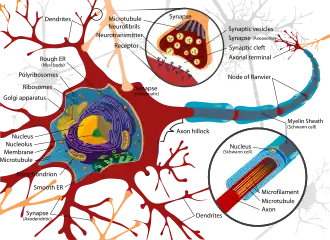

Neurotoxins inhibit neuron control over ion concentrations across the cell membrane,[6] or communication between neurons across a synapse.[13] Local pathology of neurotoxin exposure often includes neuron excitotoxicity or apoptosis[14] but can also include glial cell damage.[15] Macroscopic manifestations of neurotoxin exposure can include widespread central nervous system damage such as intellectual disability,[5] persistent memory impairments,[16] epilepsy, and dementia.[17] Additionally, neurotoxin-mediated peripheral nervous system damage such as neuropathy or myopathy is common. Support has been shown for a number of treatments aimed at attenuating neurotoxin-mediated injury, such as antioxidant[8] and antitoxin[18] administration.

Though diverse in chemical properties and functions, neurotoxins share the common property that they act by some mechanism leading to either the disruption or destruction of necessary components within the nervous system. Neurotoxins, however, by their very design can be very useful in the field of neuroscience. As the nervous system in most organisms is both highly complex and necessary for survival, it has naturally become a target for attack by both predators and prey. As venomous organisms often use their neurotoxins to subdue a predator or prey very rapidly, toxins have evolved to become highly specific to their target channels such that the toxin does not readily bind other targets[29] (see Ion Channel toxins). As such, neurotoxins provide an effective means by which certain elements of the nervous system may be accurately and efficiently targeted. An early example of neurotoxin based targeting used radiolabeled tetrodotoxin to assay sodium channels and obtain precise measurements about their concentration along nerve membranes.[29] Likewise through isolation of certain channel activities, neurotoxins have provided the ability to improve the original Hodgkin-Huxley model of the neuron in which it was theorized that single generic sodium and potassium channels could account for most nervous tissue function.[29] From this basic understanding, the use of common compounds such as tetrodotoxin, tetraethylammonium, and bungarotoxins have led to a much deeper understanding of the distinct ways in which individual neurons may behave.

As neurotoxins are compounds which adversely affect the nervous system, a number of mechanisms through which they function are through the inhibition of neuron cellular processes. These inhibited processes can range from membrane depolarization mechanisms to inter-neuron communication. By inhibiting the ability for neurons to perform their expected intracellular functions, or pass a signal to a neighboring cell, neurotoxins can induce systemic nervous system arrest as in the case of botulinum toxin,[13] or even nervous tissue death.[30] The time required for the onset of symptoms upon neurotoxin exposure can vary between different toxins, being on the order of hours for botulinum toxin[18] and years for lead.[31]